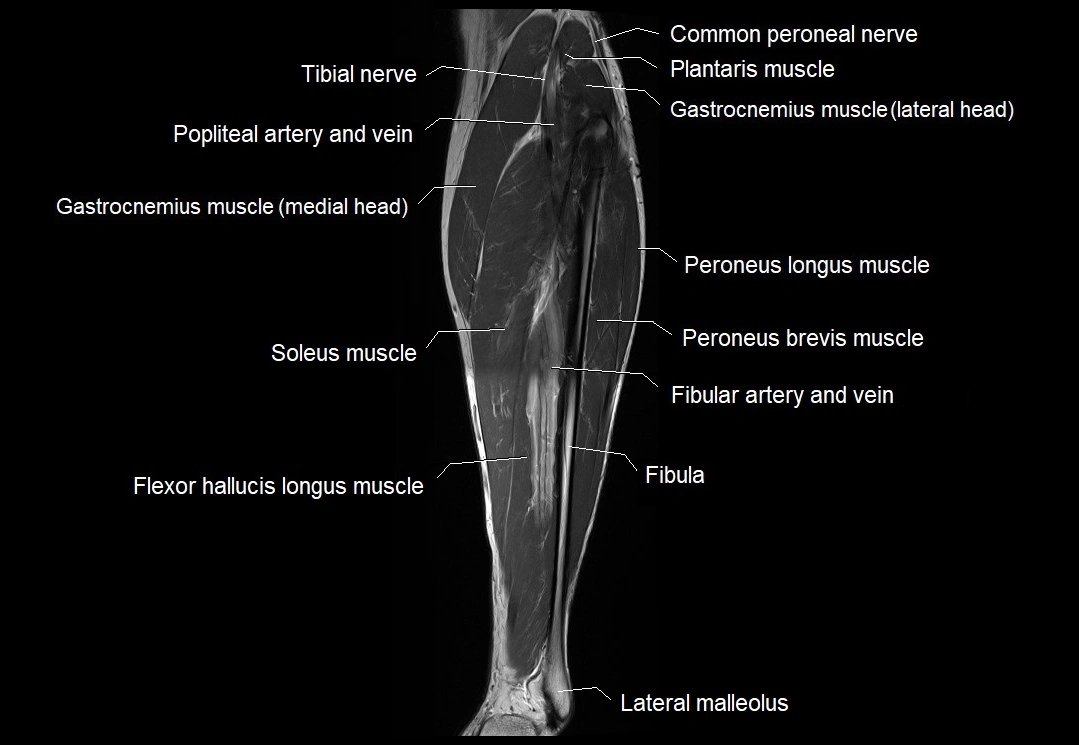

MRI image